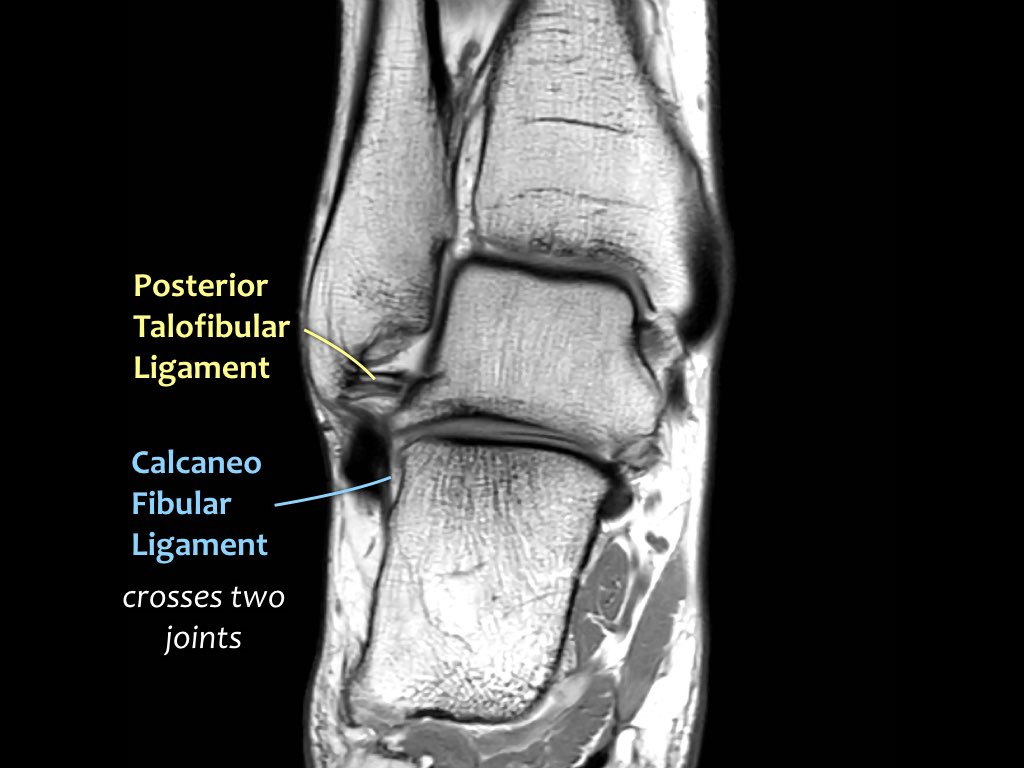

Có ba dây chằng ở phía ngoài:

- Dây chằng sên mác trước (anterior talofibular ligament – ATFL)

- Dây chằng gót mác (calcaneofibular ligament – CFL)

- Dây chằng sên mác sau (posterior talofibular ligament – PTFL).

Dây chằng ATFL chạy từ mắt cá ngoài ra phía trước đến bờ ngoài của xương sên.

Dây chằng này có hướng nằm ngang và được quan sát rõ nhất trên ảnh cắt ngang.

Đây là dây chằng bị tổn thương thường gặp nhất ở cổ chân và cũng là dây chằng đầu tiên bị tổn thương ở phía ngoài.

Điều này có nghĩa là khi dây chằng CFL hoặc PTFL bị tổn thương, rất có khả năng dây chằng ATFL cũng đã bị tổn thương.